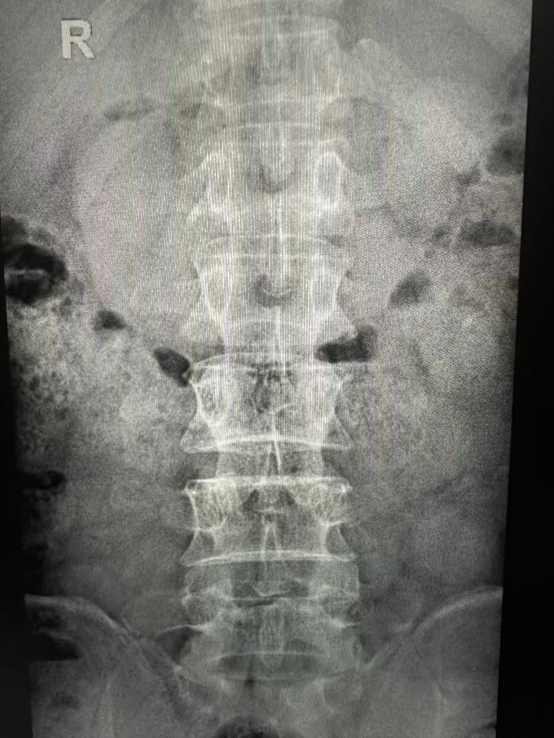

1.X线检查:

X线片可以清晰显示腰椎的骨骼结构,如椎体形态、椎间隙宽度、有无骨质增生、腰椎的生理曲度是否改变等。虽然X线不能直接看到椎间盘,但能为医生判断腰椎的整体形态和稳定性提供重要依据,对于发现腰椎骨折、脱位、脊柱侧弯等问题有很大帮助 。